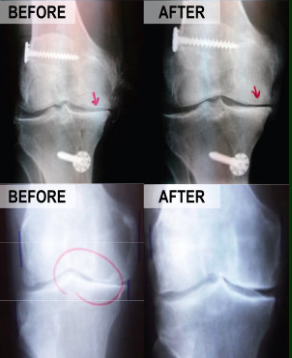

Scientific Advancements in Regenerative Medicine to Avoid Knee Surgery

Utilizing advancements in technology, scientists have discovered how to harness the human body’s natural ability to heal and direct those cells to stimulate regeneration of chronically injured tissues. These procedures are far less invasive than their surgical alternatives, resulting in significantly less pain following the procedure and far faster recovery times.

Utilizing the same technologies currently being used at major medical facilities such as the Mayo Clinic, Dr. Morales will remove and isolate the cells in your body responsible for stimulating the healing process prior to re-injecting them directly into your damaged tissues. All injections are performed with ultrasound or fluoroscopic (x-ray) guidance to assure precise localization of the injection into the exact location of the damage. The Regenerative Medicine procedures performed in our clinic are medically proven, with new studies being published monthly in major medical journals.